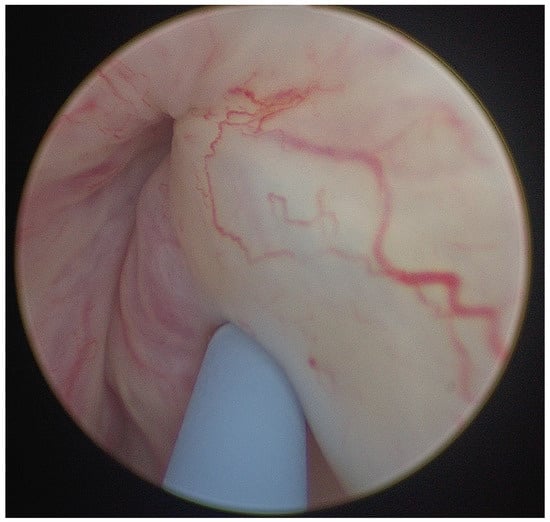

Compression of the left renal vein between the abdominal aorta and superior mesenteric artery, known as nutcracker syndrome, can present with subtle, nonspecific symptoms that often delay diagnosis, posing a clinical challenge in daily urology practice and necessitating targeted imaging for accurate identification.

Compression of the left renal vein between the abdominal aorta and superior mesenteric artery, known as nutcracker syndrome, can present with subtle, nonspecific symptoms that often delay diagnosis, posing a clinical challenge in daily urology practice and necessitating targeted imaging for accurate identification. We report the case of a 39-year-old patient who presented with isolated hematuria and long-standing pelvic pain and was ultimately diagnosed with nutcracker syndrome. Following the failure of endovascular therapy, the patient underwent renal autotransplantation, resulting in complete resolution of symptoms at follow-up.